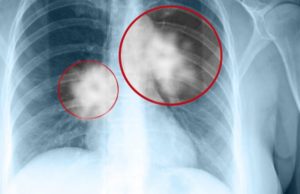

Cancer pulmonar: simptome și persoane cu risc

Cancer pulmonar: simptome, persoane cu risc. Uneori, nu sunt detectabile simptome. Cele mai frecvente simptome sunt următoarele:

Tusea care se intensifică sau nu dispare (trebuie...